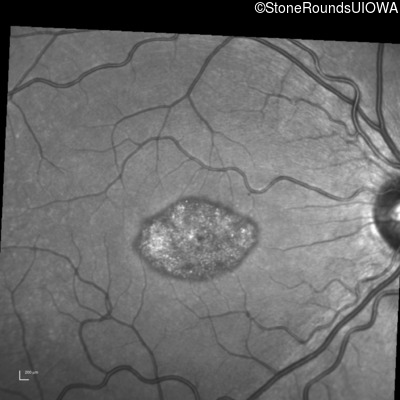

This 22 year old man had macular abnormalities noted incidentally at a routine eye exam at age 19. Since then, he has experienced a gradual loss of acuity particularly in the left eye.

| Disease | Gene | Allele 1 variant(s) | Allele 2 variant(s) | Inheritance mode |

|---|---|---|---|---|

| AR Stargardt Disease | ABCA4 | Tyr245Stop TAT>TAG | Unknown | AR |